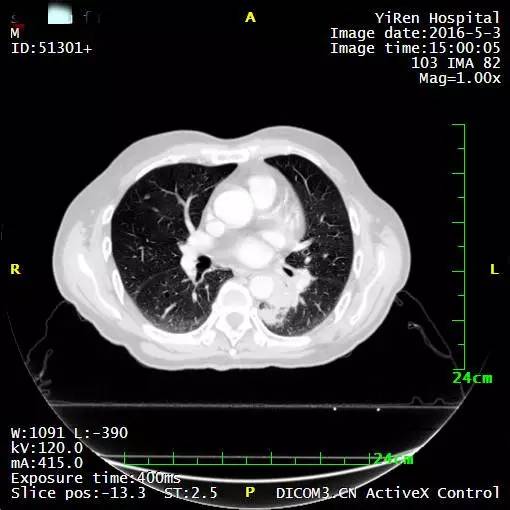

2、张女士,50岁体检时发现发现肺部结节,2016年5月,PET-CT诊断:右肺癌治疗后,双肺复发、右侧肾上腺多发转移灶,接受A45肿瘤治疗复查结果显示肺上三个病灶消退。

左图红色圈内是A45治疗前三个肺癌病灶,右图为治疗后病灶消失